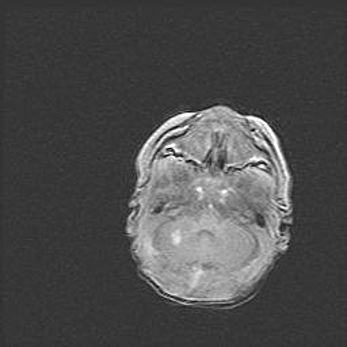

Подострая гематома правой гемисферы мозжечка.

Наружная гидроцефалия.

Возраст: 15 дней

Вес: 3100 г

Пол: женский

Окружность головы: 37 см

Срок гестации: 35-36 недель

При открытой наружной форме гидроцефалии у новорожденных расширяются и переполняются субарахноидные пространства.

Кровоизлияния в мозжечок имеют две клинико-анатомические формы: полушарные гематомы и кровоизлияния в червь.

К появлению этой патологии может привести: повреждения головного мозга, возникающие в результате асфиксии и гипоксии плода при беременности, или травмы во время родов. Редко гематома мозжечка может быть результатом первичной коагулопатии и сосудистой мальформации, диссеминированном внутрисосудистом свертывании, изоиммунной тромбоцитопении.